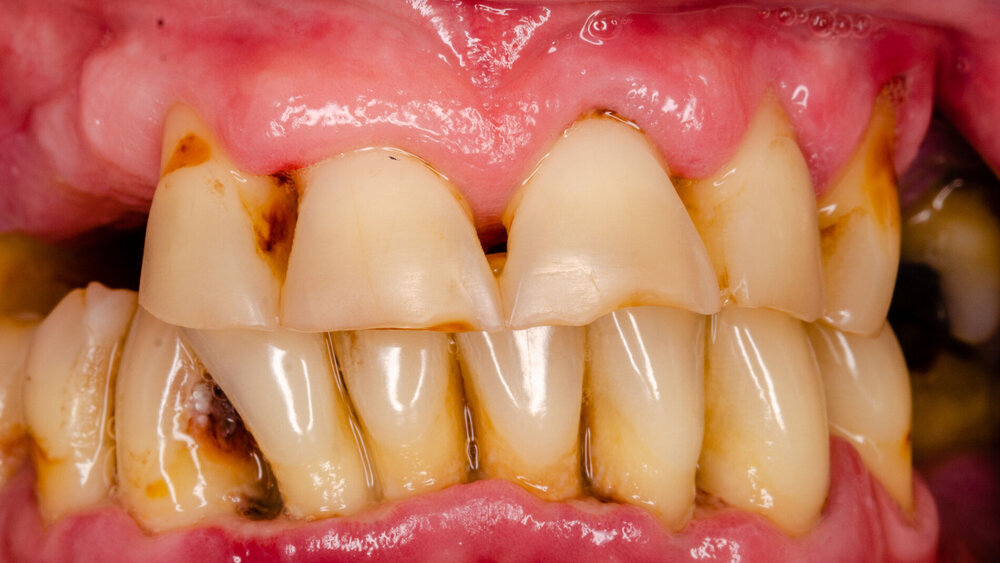

Parodontitis: Topisches Gel in vitro erprobt

Neue Forschungsergebnisse der New York University zeigen die Wirksamkeit einer nicht-invasiven Behandlung von Parodontitis, die an Mäusen und unter Verwendung humaner Zellen und Plaque-Proben durchgeführt wurde.